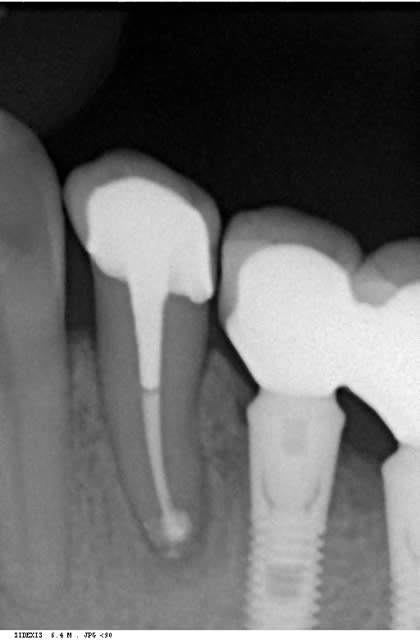

un cas comme je les aime......

bon, une petite pensée pour mon pote athos.....